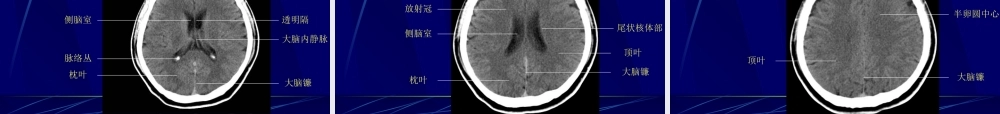

中枢神经系统正常及异常影像改变北京协和医院放射科中枢神经系统影像学技术颅骨平片脑血管造影脑CT脑磁共振头颅平片(正侧位像)头颅平片诊断价值有限•观察异物的存在和骨质结构的明显变化显示骨折、肿瘤骨转移、网状内皮系统疾病、代谢性骨病、骨纤、畸形性骨炎等观察颅骨骨折,有学者建议直接行CT•注意辨别正常颅缝、血管沟和骨折线•有时可看见颅内钙化,如松果体钙化、肿瘤钙化等(中线钙化:松果体钙化、第三脑室脉络丛钙化、大脑镰钙化)•侧位可观察蝶鞍的形态,如扩大提示垂体瘤等,但不扩大也不能排除病变脑血管造影脑血管造影适应征•诊断脑动脉瘤、血管发育异常、血管闭塞•了解脑肿瘤的供血动脉•可同时行介入治疗溶栓Coil(螺圈)闭塞动脉瘤和血管畸形等术前栓塞富血管性肿瘤如脑膜瘤其他NeuroCT----CT在CNS的应用•CT平扫怀疑急性颅内出血的首选检查手段若CT已有梗塞征象,则不应系统溶栓•CT血管造影(CTangiography,CTA)识认血管•其他最新应用CT脑灌注成像(CTperfusion)MRItips•主要基于3个可变的生物学参数:质子密度(protondensity)纵向驰豫恢复时间(T1relaxationtime)横向驰豫恢复时间(T2relaxationtime)•通过采用不同的脉冲序列和不同的成像参数,获得反映上述生物学参数对比的MR图像,即质子密度加权像(PDWI)、T1加权像(T1WI)和T2加权像(T2WI)•这些图像上的信号强度与特定的组织特征有关。比如:血肿的化学和物理结构随时间而变化,直接影响其MR图像的信号强度由此提供出血时间的信息,急性?亚急性?还是慢性?其他方法•气脑造影及脑池造影Airencephalographyandcisternography有创性检查,现已基本不用。•USG用于囟门未闭的婴幼儿,观察脑内结构;TCD:检测颈部及颅内动脉血流动力学变化,了解头颈部血管病变的情况。PartII:imagingfeatures中枢神经系统正常及异常影像学表现MRI图像T1加权像:--看正常解剖---脑脊液和房水是黑的灰质比白质暗(就像真的)T2加权像:--看病理改变---脑脊液和房水是白的灰质比白质亮骨皮质骨髓质脑膜脑脊液脑白质脑灰质血管T1WI低信号高信号低信号低信号高信号等信号流空信号T2WI低信号中高信号低信号高信号等信号中高信号流空信号颅脑正常的MRI信号颅脑X线解剖简介平片-正位像平片-侧位像CT-颅底蝶鞍层面蝶骨小翼前床突颞骨岩部脑桥小脑半球枕内隆凸第四脑室颞叶鞍上池层面额叶颞叶鞍上池脑桥第四脑室小脑半球额窦第三脑室层面侧...